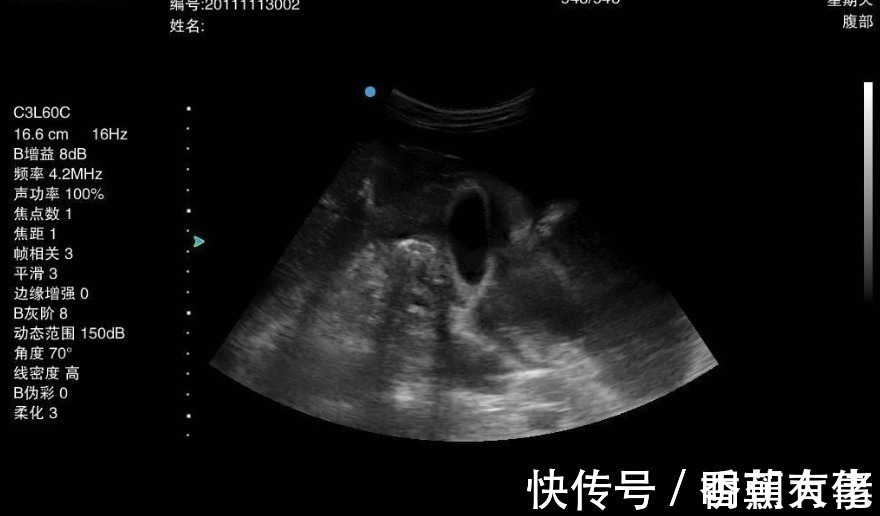

到医院后,医生建议他做一个胃镜检查,这一检查才知道,小金得了胃癌,小金很疑惑:近年来饮食上都很清淡,没有乱吃什么,就是有一个单纯的胃炎病,怎么还变成胃癌了呢?